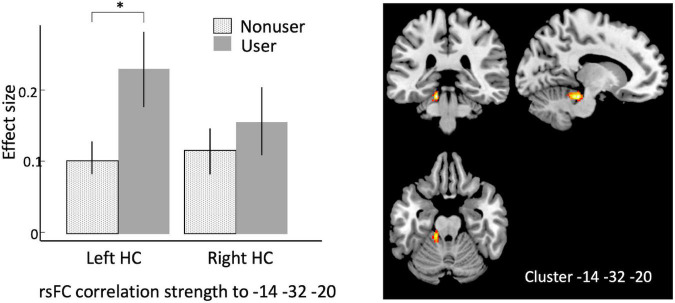

Using bilateral hippocampus as seed regions, a single cluster of voxels yielded rsFC values that were significantly associated with cannabis use. A cluster in left cerebellum (MNI coordinates –14, –32, –20; 101 voxels; p-FWE = 0.027) had significantly increased rsFC with left hippocampus in users vs. non-users (Figure 1 and Table 1).

To expand on this finding, we next performed an analysis using the CONN built-in ROI atlas of 164 brain regions, based on the Harvard-Oxford atlas for cortical and subcortical regions, and the Automated Anatomical Labeling (AAL) atlas for cerebellar subregions. In this analysis, we chose six a priori seed regions consisting of bilateral hippocampus, posterior parahippocampal cortex (pPaHC), and anterior parahippocampal cortex (aPaHC). ROI-to-ROI analyses take the mean resting brain activity across all the voxels within each anatomically defined source ROI and correlates this with the mean brain activity across voxels in each anatomically defined target ROI. Consistent with our seed-to-voxel analysis, we found stronger connectivity with anterior cerebellum (lobules III and IV/V and vermis IV/V; Figure 2 and Table 2).